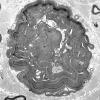

1B10 HNPP (Case 1) EM 1 - Copy